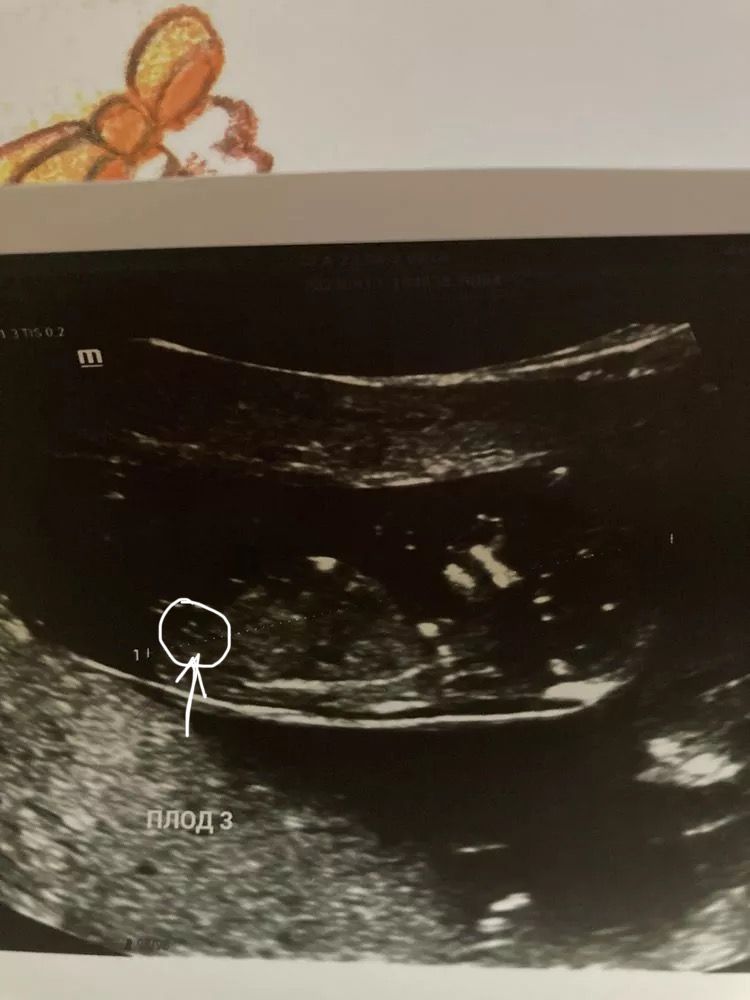

это ножка так торчит,а бугорок там видно,но ракурс не самый удачный,не очень понятно под каким он углом.От всей души желаю вам девчонок!!! Изображение

Anya, я тоже после 1 скрининга по 100 раз пересматривала ,но тут больше на ножку похоже ,неделек в 15-17 переделайте.Что б уж точно

Катерина, мне в 13,6 говорили что видно .Но тройня возможно мельче ))

Катерина, согласна,но в целом если узист хороший под в 13 недель уже видно